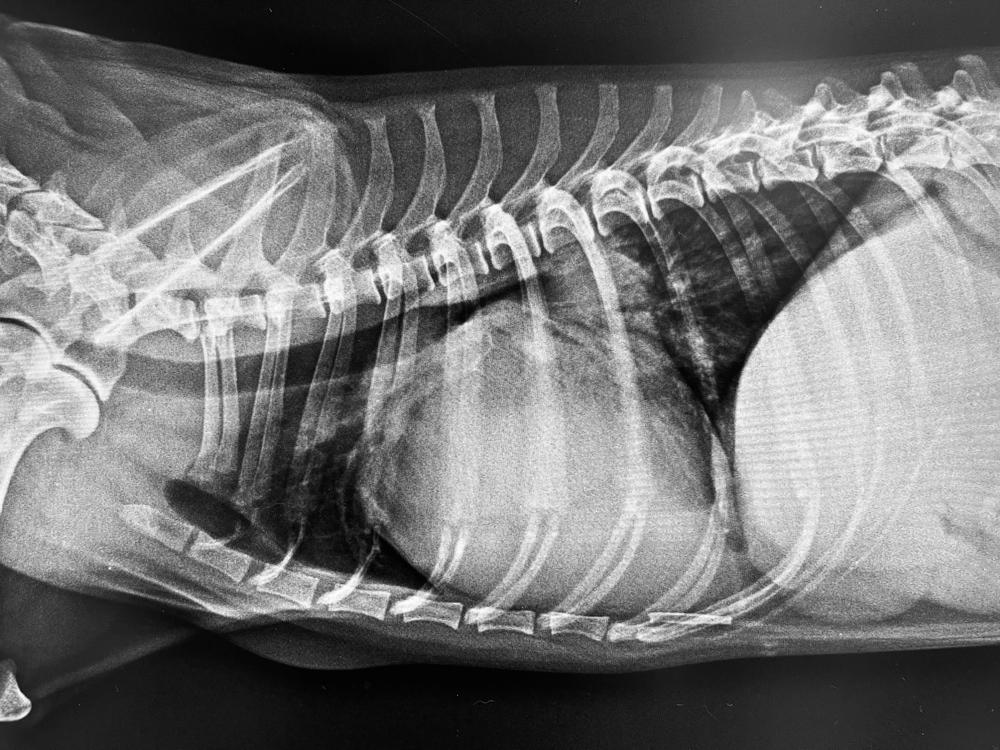

Рентген грудной клетки. Изучает костные структуры и мягкие ткани дыхательных путей. Необходим для определения нарушений в легких.

-